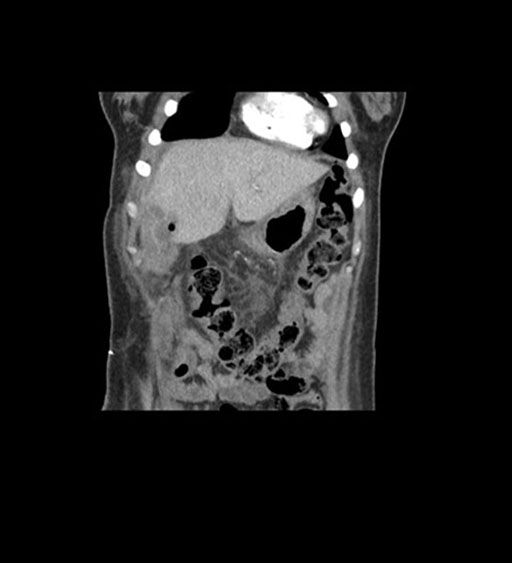

Coronal Venous

Imaging analysis

Based on initial findings, which issue(s) would you be most concerned about?